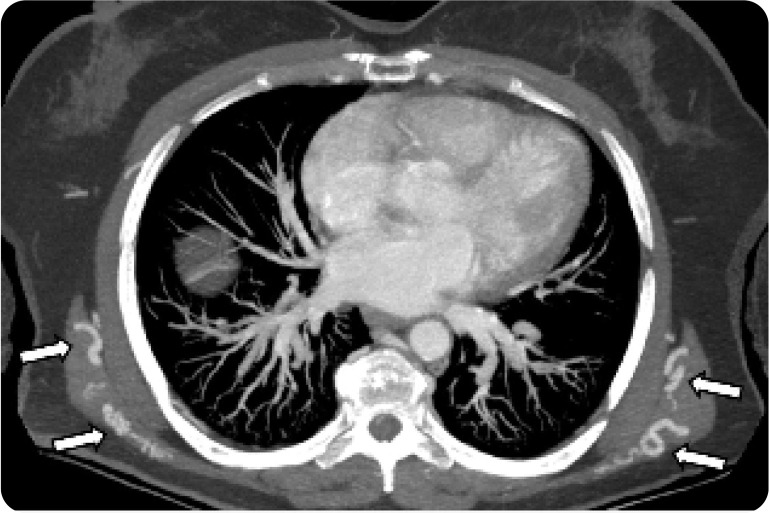

Abstract Image